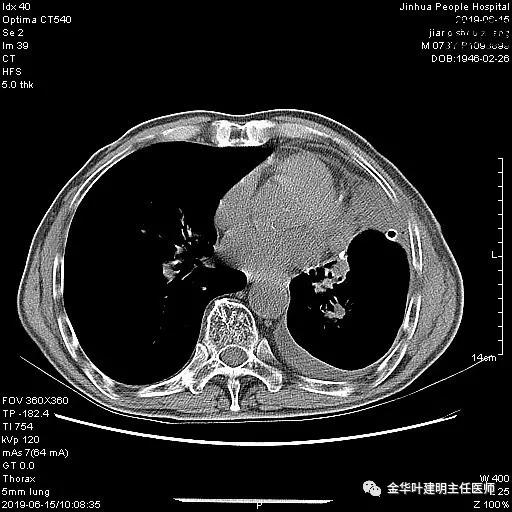

考虑左侧大量胸腔积液,遂进一步胸部CT检查:

以上是肺窗表现,下面为纵隔窗影像: